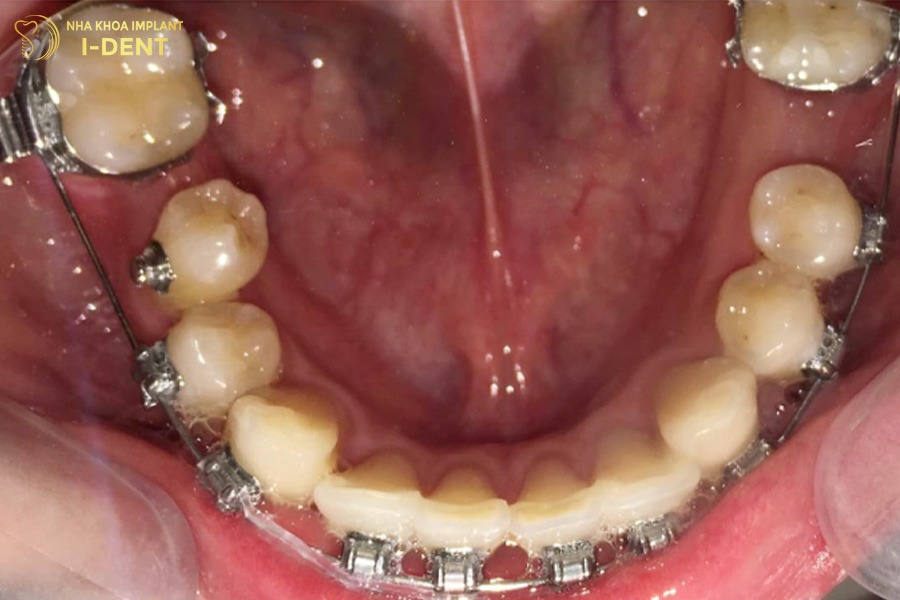

- Niềng răng mắc cài: Đây là phương pháp niềng răng truyền thống, sử dụng lực tác động của mắc cài cùng dây cung để kéo chỉnh răng về vị trí chuẩn. Mắc cài có nhiều loại khác nhau như mắc cài kim loại bền chắc, mắc cài tự động điều chỉnh răng với tốc độ nhanh hoặc mắc cài sứ mang đến sự thẩm mỹ. Giá niềng răng mắc cài có chi phí thấp hơn các phương pháp chỉnh nha khác nên được nhiều bệnh nhân lựa chọn.

Niềng răng trong suốt Invisalign diễn ra đơn giản vì mỗi khay niềng đều được sản xuất và đánh thứ tự sẵn, bạn chỉ cần đeo và thay khay định kỳ theo đúng yêu cầu của bác sĩ. Trong khi đó, với phương pháp niềng răng kim loại và niềng răng sứ, bác sĩ sẽ gắn mắc cài lên thân răng bằng composite, sau đó luồn dây cung vào rãnh mắc cài rồi cố định lại bằng dây thun.

Quá trình niềng răng mắc cài chỉ kéo dài trong vài giờ và không khó chịu hay quá đau nhức. Sau đó, bạn chỉ cần chăm sóc tốt răng niềng và đến nha khoa tái khám theo đúng lịch hẹn để bác sĩ kiểm tra và tiến hành điều chỉnh lực siết.

Bác sĩ đang tiến hành niềng răng cho bệnh nhân